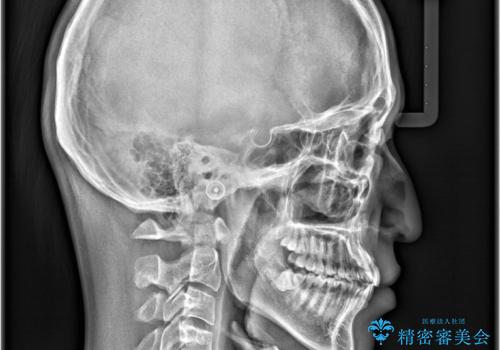

インビザラインで叢生の改善を行いました。

歯は抜かずに、拡大と少しのIPRで並べました。

矯正期間は半年です。